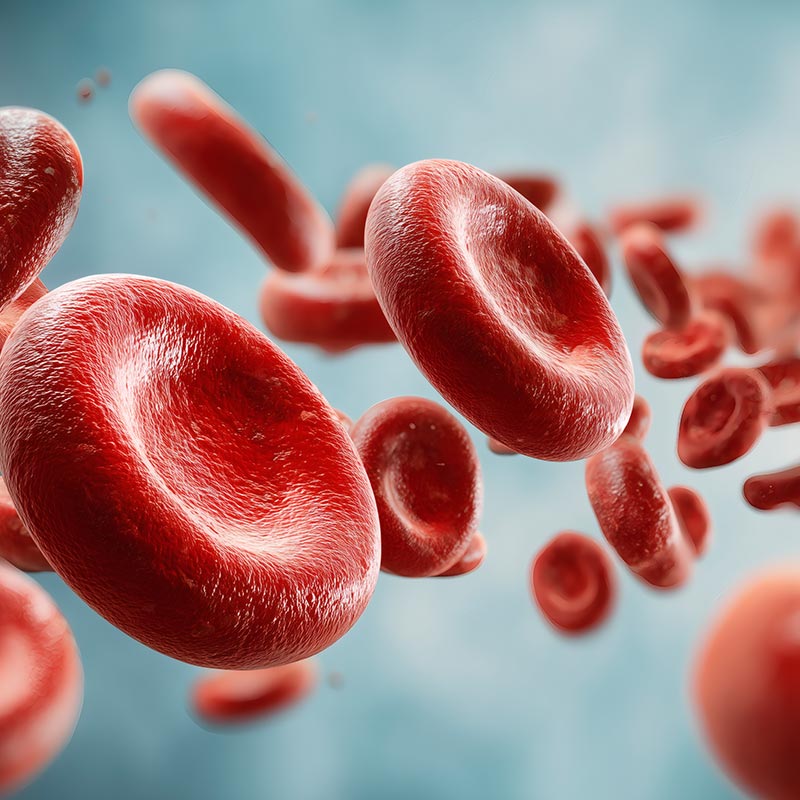

혈액투석은 몸속에 쌓인 노폐물과 과도한 수분을 제거해 아이의 소중한 생명을 지키는 치료입니다.

혈액 투석이 지시되는 환자의 경정맥에 혈액 투석 카테터를 장착한 후 혈액 투석을 시작합니다.